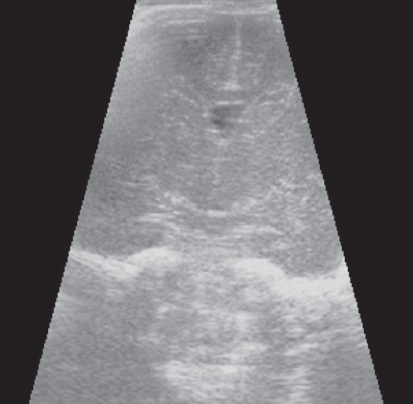

Patterns of neuroplasticity and cerebral maturation in preterm neonate can be assessed by MRI and cranial ultrasound. The score system of brain maturation includes the account of germinal matrix (GM) regression by MRI. The GM regression can be considered as pattern of neuroplasticity. There have been investigated the changes of neuroplasticity pattern or GM regression in preterm neonates with extremely low birth weight (ELBW) without intragerminal/intraventricular hemorrhages (n = 21). It is believe that the main causes of impair of GM are the intragerminal hemorrhages and hypoxia. The methods of study were cranial ultrasound (CU) and MRI. The measurement of GM was carried out by CU in anterior horn of the lateral ventricles of neonates in the study group (25-29 weeks). It was detected the GM regression in preterm neonates with increasing age, and complete GM regression to 30 week. MRI has been performed in 15 neonates from the study group on 27-38 weeks age with using the common pulse sequences – T1 WI, T2 WI and Flair. GM was detected by MRI up to 34 weeks inclusive by using the additional pulse sequence – DWI. By using common pulse sequences the GM was visualized up to 32 weeks age. Furthermore there has been pathological examination of GM in anterior horn of lateral ventricle in dead neonates from the study group (n = 3). We revealed the thickness reduction of GM in the lateral ventricles with increasing age of the dead neonates. Also we identified the delay of the GM reduction in two dead neonates 36-38 weeks age (post conceptual age) what may indicate the disorder of neuroplasticity in those preterm neonates. The performed study showed the capability of CU and MRI in examination of neuroplasticity in preterm neonates.